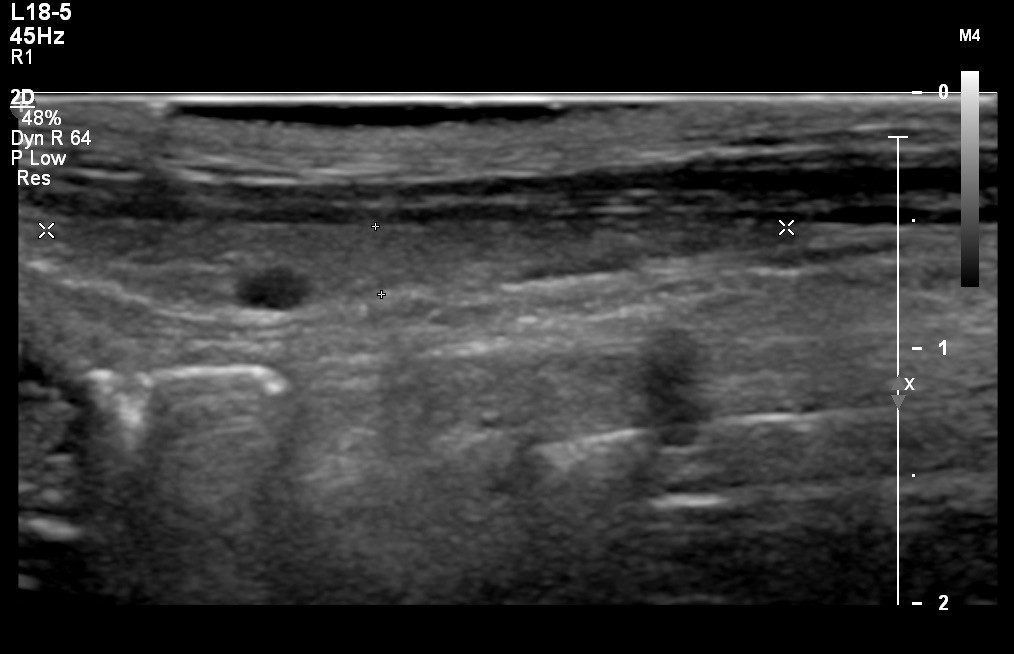

Imaging will include evaluation of the liver, gallbladder and biliary tract, kidneys, adrenal glands, urinary bladder, prostate gland, reproductive tract, gastrointestinal tract, pancreas, intra-abdominal lymph nodes, great vessel, and mesentery. Ultrasound examinations for portosystemic shunts are also available. If warranted, ultrasound-guided aspirates and/or biopsies can be performed subsequent to the initial scan.

Micro-convex, linear and convex probes are used alone or in combination in an effort to visualise all intra-abdominal structures.